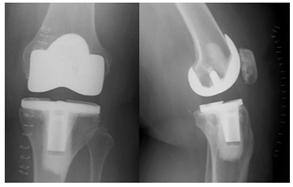

She did well for a year and a half following her revision surgery then presented with knee pain located medially on the joint line, over the pes bursae as well as along her distal IT-band. It was also noted in flexion that her excess soft tissue from her posterior thigh impinged on her posterior leg. Radiographs were obtained (Figure 3), and revision surgery to a hinge type knee was recommended to control AP instability, particularly given the posterior impingement of her soft tissues in the popliteal region secondary to her body mass distribution, which on exam appeared to be causing anterior tibia translation and likely contributing to the catastrophic posterior medial tibia failure.

The patient waited, given her symptoms at this time frame were only mild; however, 4 months later she presented for follow up, as she was having significant instability (Figure 4). She was then scheduled for revision TKA.

Figure 3 AP/Lateral left knee, 16months following revision surgery, again demonstrating anterior tibia translation and joint line asymmetry concerning for mechanical failure of the polyethylene.

Figure 4 AP/Lateral left knee 20months from revision surgery demonstrating increased anterior tibia subluxation and medial joint space narrowing. There is also evidence of posterior medial tibia tray fracture.